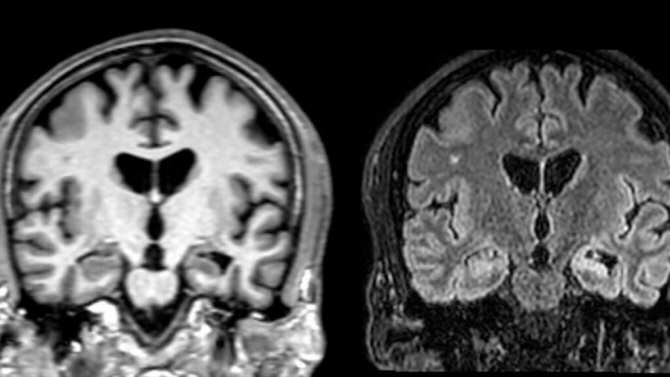

El test és capaç de distingir diferents subtipus d’apatia en els pacients de Huntington, el que obre noves perspectives a entendre aquesta simptomatologia considerada un marcador de progressió.

A més, l’estudi defineix certa correspondència entre cada subtipus apàtic i l’activació d’una regió cerebral determinada. «